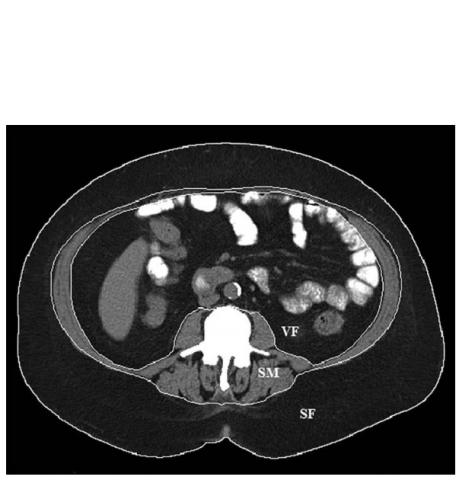

- les changements dans la composition corporelle sont surprenants : l'indice de masse musculaire squelettique (SM sur visuel ci-dessous), une mesure de la quantité de muscle lié au squelette qui contribue à la motricité, est réduit de 6,8%. Or une perte de muscle squelettique peut altérer la fonction physique et le métabolisme et accroître le risque de chute et de blessure.

La perte de graisse corporelle est confirmée et conséquente : l’étude confirme l’efficacité de la procédure pour la perte de masse graisseuse. En effet, le taux de masse grasse est réduit, en moyenne chez ces patients, de 3,7%. Cependant, la plus grande partie de la perte de graisse consiste en graisse sous-cutanée (subcutaneous fat ou SF sur visuel ci-dessous), et non en graisse viscérale (visceral fat ou VF sur visuel ci-dessous), la graisse la plus dangereuse entourant les organes et associée aux problèmes de santé sévères comme les maladies cardiaques et le diabète. Or cette graisse viscérale ne diminue pas de manière significative au cours du suivi.